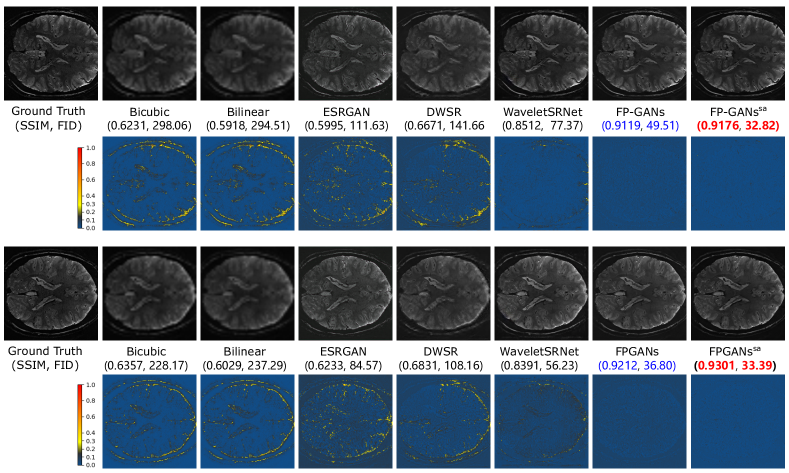

Figure 7: Difference comparison among Bicubic, Bilinear, ESRGAN, DWSR, WaveletSRNet, FP-GANs and FP-GANssa with heatmap. Brighter pixel means more difference to the ground truth.

As illustrated in Figure 6, the interpolation based methods produce over-smooth results. GAN based method—ESRGAN reproduces rich textures though, the result loses its coherency with the input. FP-GANs recovers finer anatomical structure with shaper and clearer textures while remaining consistency. To further examine the detail capture ability, difference heatmap, reflecting absolute difference between generated image and corresponding ground truth, is utilized as Figure 7 shows. It can be apparently observed that there is less difference in the heatmap of FP-GANs and FP-GANssa than the competing methods. This confirms the detail sensitivity of the proposed structure.